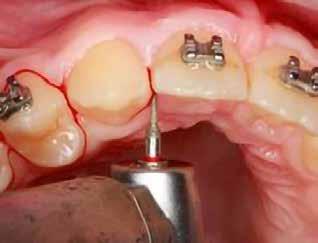

Szemfog becsiszolás

A szemfog elcsiszolásához piros gyémántfúró javasolt, finom szemcsézettséggel, 27-76 µm (okkluzálisan lekerekített – Rodentica, speciális hegyű 806314466514031, Komet 8833), gyorsítóval (max 160 000 fordulat/perc) megfelelő hűtés mellett, legalább 50 ml/perc. Ezt követi a felület kidolgozása és polírozása sárga gyémántcsiszolóval, extra finom szemcsézettséggel, 10-36 µm (Rodentica 806314466504031) és narancssárga Sof-Lex korongokkal (finom alumínium-oxid szemcsék 3-40 µm, extra finom, narancssárga-sárga, alumínium-oxid kristályok mérete 1,7 µm) könyökdarabban (25000 fordulat/perc) megfelelő hűtés mellett min. 50 ml/perc (2. a-d. ábra).

2. a–d ábrák